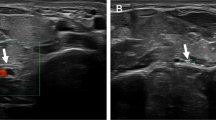

Intraoperative stimulation of brachialis branches showed excellent motor response. Intraoperative stimulation of the median nerve motor fascicles produced contraction of flexor pollicis longus (FPL), flexor digitorum profundus (FDP) to index and long finger, and FDS. A brachialis nerve transfer to both the AIN and FDS nerve fascicles of the median nerve was undertaken (Fig. 3) (Video 1S).

Figure demonstrates the donor brachialis branches of the musculocutaneous nerve, and the recipient FDS and AIN fascicles of the median nerve. Intraoperative measurement revealed 14–16 cm of nerve regeneration required from coaptation to target muscle re-innervation (Reprinted with permission. Copyright 2018, nervesurgery.wustl.edu).

Intraoperative stimulation of donor showed a strong response to the supinator muscle. Intraoperative stimulation of the PIN induced very weak thumb extension via extensor pollicis longus (EPL) only and no stimulation of the extensor digitorum comminis (EDC). A supinator to PIN transfer was undertaken to restore hand opening (Fig. 4) (Video 2S).

Figure demonstrates proximally the donor supinator nerve and distally the recipient PIN. Intraoperative measurement revealed 2–4 cm of never regeneration required to reach target muscle (Reprinted with permission. Copyright 2018, nervesurgery.wustl.edu).